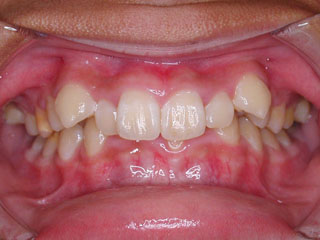

主訴:上顎前歯の突出 口が閉じにくい

診断名:叢生と伴う上顎前突

年齢:13歳

使用した主な装置名:TPB、HG、マルチブラケット装置

抜歯/非抜歯および抜歯部位:抜歯(上顎左右第一小臼歯)

治療期間:動的処置2年6か月、経過観察3年6ヶ月

費用の目安:90~140万円

リスク、副作用:抜歯によるリスク、マルチブラケット治療に伴う歯根吸収など偶発症が発生するリスクがある。

上顎前歯の前突が見られます。下の歯には中程度の叢生と口唇前突感がみられました。分析結果では、2級1類と呼ばれるタイプの不正咬合でした。上顎の左右第一小臼歯を抜歯してマルチブラケット治療を行いました。